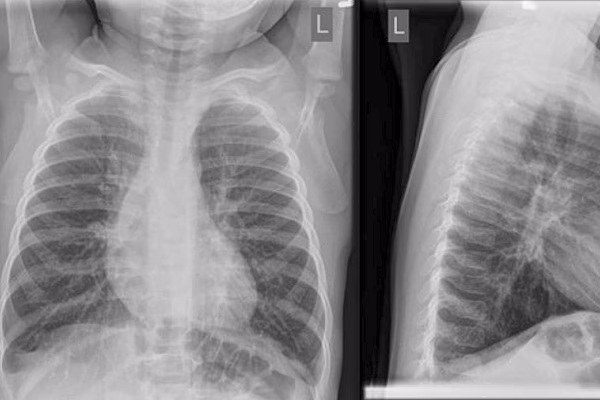

Et røntgenbillede af brystkassen er en hurtig og smertefri procedure, der bruger en lille mængde ioniserende stråling til at skabe billeder af kroppens indre strukturer. For lungerne er det et uvurderligt værktøj. Sunde lunger er fyldt med luft og fremstår derfor mørke på et røntgenbillede. Når der er en infektion, som ved lungebetændelse, vil det betændte område blive fyldt med væske og celler, hvilket gør det tættere. Dette tættere væv absorberer mere stråling og fremstår som et lysere eller hvidt område på billedet. Dette fænomen kaldes en pulmonal fortætning eller et infiltrat.

Når en radiolog beskriver en pulmonal fortætning på et røntgenbillede, betyder det simpelthen, at et område af lungen er blevet uigennemsigtigt eller uklart. Selvom dette er det klassiske tegn på lungebetændelse, er det vigtigt at forstå, at det ikke er en specifik diagnose i sig selv. Fortætningen skyldes, at alveolerne er fyldt med noget andet end luft. Der kan være flere årsager til dette, og lægen bruger de kliniske symptomer til at finde den mest sandsynlige forklaring.

Hos et barn med feber, hoste og en blodprøve, der viser et forhøjet antal hvide blodlegemer (leukocytter), vil en pulmonal fortætning på et røntgenbillede med meget stor sandsynlighed pege diagnosen i retning af lungebetændelse.